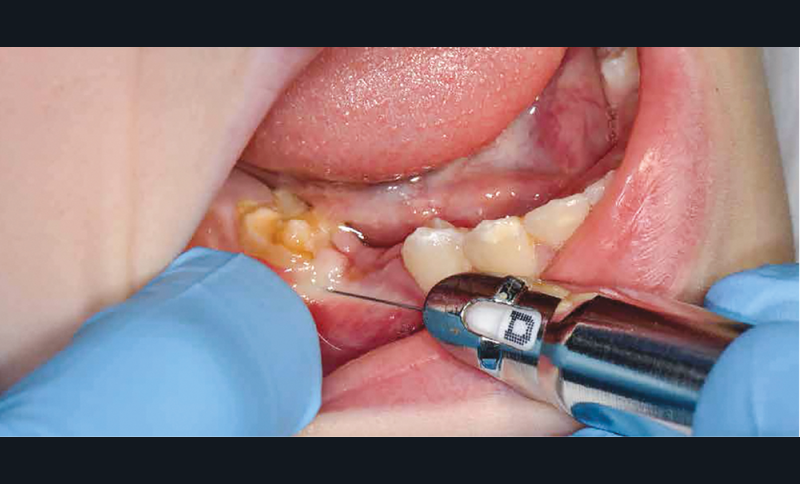

Parmi les techniques d’anesthésie qui s’offrent à nous, l’anesthésie ostéocentrale apparaît comme fiable, facile à mettre en place, immédiate et bien acceptée chez l’enfant [4-6].

Afin d’optimiser les séances de soins, l’anesthésie intra-osseuse par injection électronique a été réalisée avec le Quicksleeper 5® dans les deux secteurs (fig. 3 et 4) afin de permettre la réalisation des coiffes préformées métalliques sur 36 et 46 dans la même séance (fig. 5 à 7). Il aurait été difficilement envisageable de réaliser les coiffes dans la même séance en utilisant une anesthésie tronculaire dans chaque secteur.